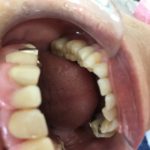

奥歯セラミック

2021年1月31日(日)

皆さまこんにちは!

この患者さまは奥歯をきれいにして堂々と

お口を開けたいとのことでした。

セラミックブリッジ

間違いないきれいさです。

セットし、この患者さまは💕

次のブログへ❤️❤️❤️❤️